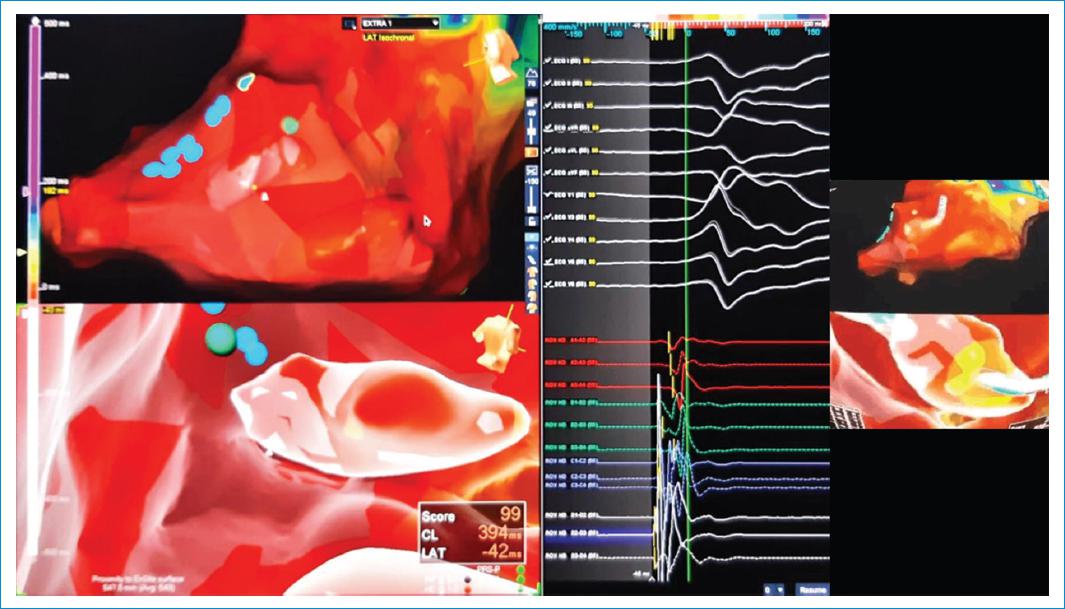

Figura 1 A la izquierda se identifica la reconstrucción anatómica tridimensional del músculo papilar anterolateral. En el centro de la imagen se aprecia la morfología de la extrasístole, así como la concordancia de la morfología (99%) al realizar el mapeo sobre dicha estructura, y a la derecha la posición del catéter durante crioablación.

Bajo visión de ecografía intracardiaca y previa aplicación de dos bolos de heparina, manteniendo ACT 300-350, se realizó punción transeptal con camisa Agilis®. Se pasó un catéter HD Grid® (EnSite Velocity and Precision, St. Jude Medical Inc.), se obtuvo mapa anatómico y mapa de activación de alta densidad del ventrículo izquierdo (10 500 puntos de activación) con catéter HD Grid® (EnSite Velocity and Precision, St. Jude Medical Inc.) observando zona de mayor preactivación en la base del músculo papilar anterolateral (Fig. 1). Se intercambió el catéter de mapeo por catéter de ablación Freezor® MAX (Medtronic), para lo cual se realizaron seis aplicaciones de 240 segundos y se alcanzaron temperaturas de hasta -75 °C, desapareciendo la extrasístole ventricular.